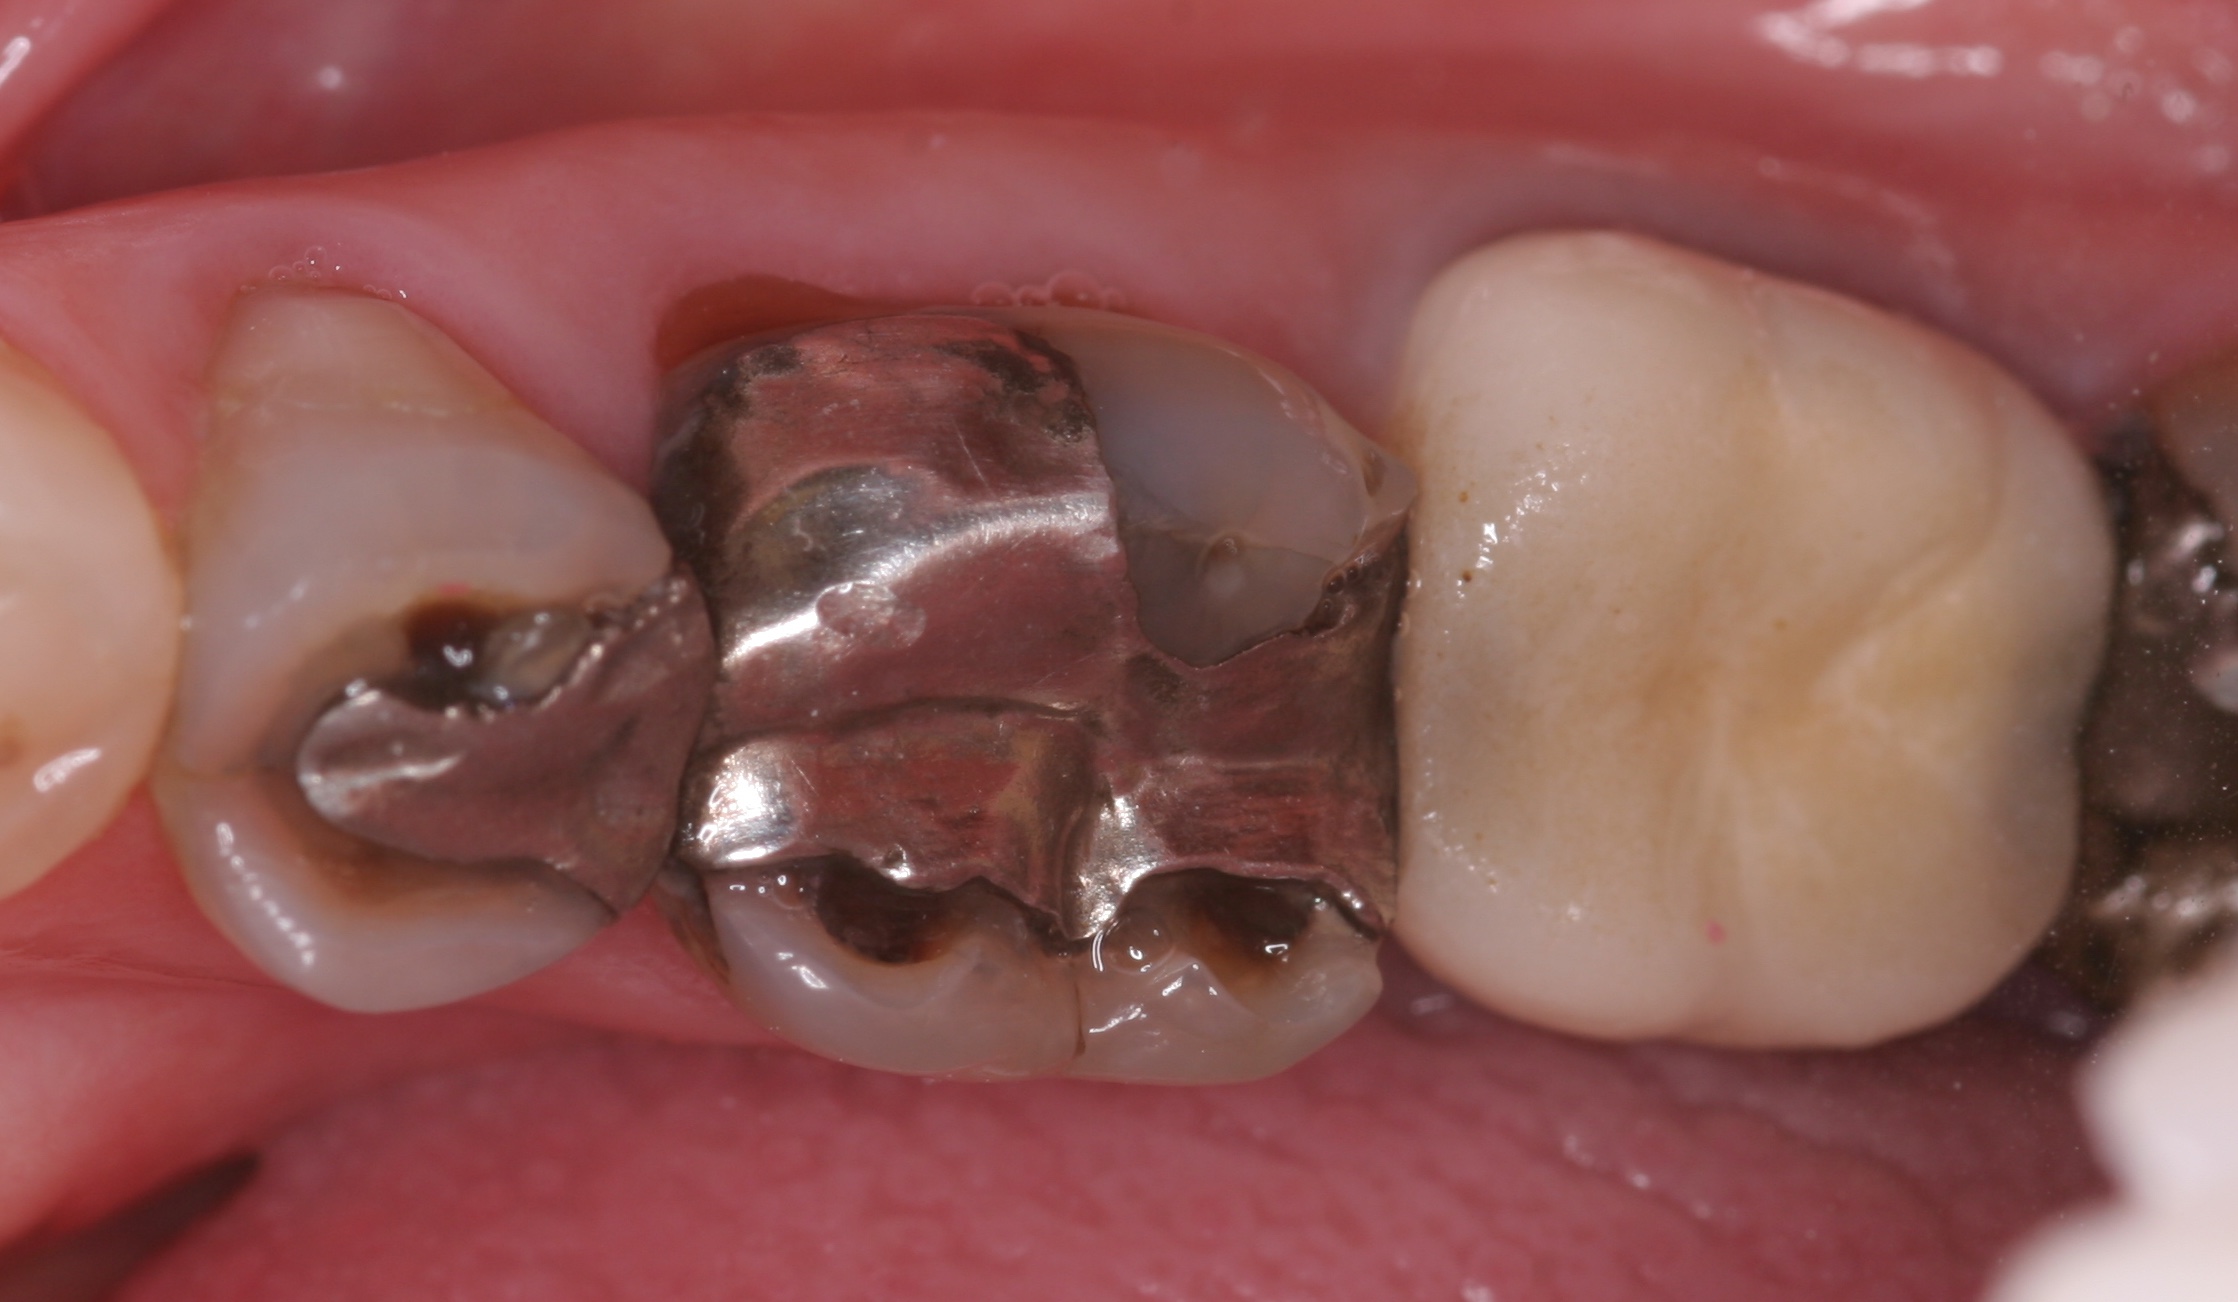

(7.) “Ditching” from GERD around existing restorations may be noted upon examination.

Figure 7

A common form of gastric erosion results from regurgitation. It presents with prominent involvement of the maxillary anterior lingual surfaces (Figure 6). Erosion starts at the gingival margin and reaches to the incisal edge. Gastric reflux disease (or “GERD”) can also cause erosion, mostly on the mandibular posterior teeth. Ditching around existing restorations may also be noted upon examination (Figure 7). A habitual pattern of “Coke swishing” may also produce varied areas of erosion.5